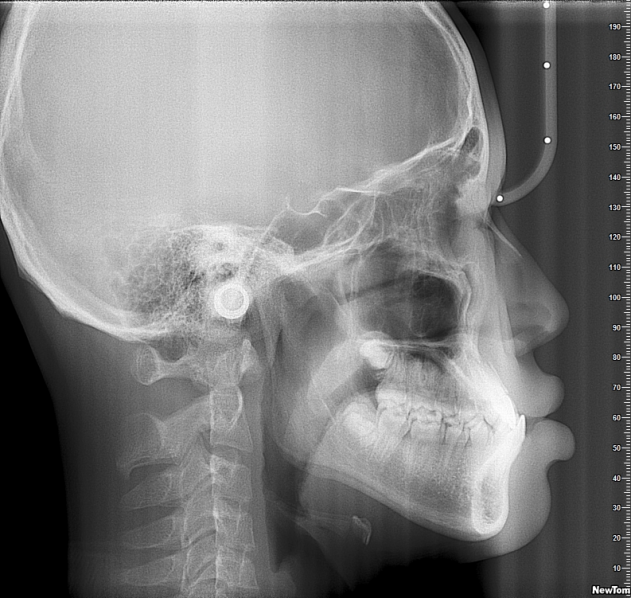

曹显介绍,目前最常见的几种需要牙齿矫正的情况包括牙齿不齐、“地包天”以及龅牙,他以“地包天”举例:“如果下颌往前伸,我们可以通过整牙来将其恢复到正常状态。”

也是因此,正畸是一个“牵一发而动全身”的矫正过程,“整牙的专业术语其实叫‘牙合重建’,相当于把房子推倒一半后重建,让其兼具美观与功能实现。”他特别提到,矫正从来都不仅仅关乎一两颗牙齿,“比如有家长说能不能只调整特别糟糕的牙,这就不符合正畸的操作了。”